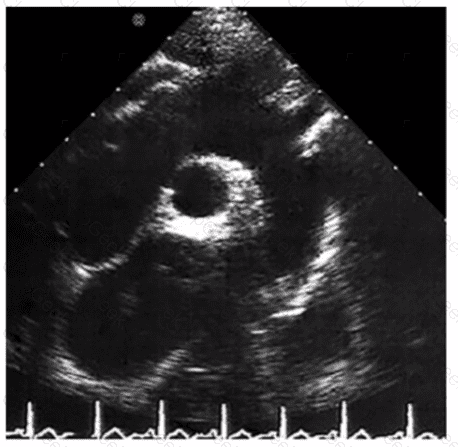

Which diagnosis is most likely confirmed by echocardiography in a 65-year-old female presenting with new onset chest pain associated with ST segment elevation on the electrocardiogram and angiographically normal coronary artenes?